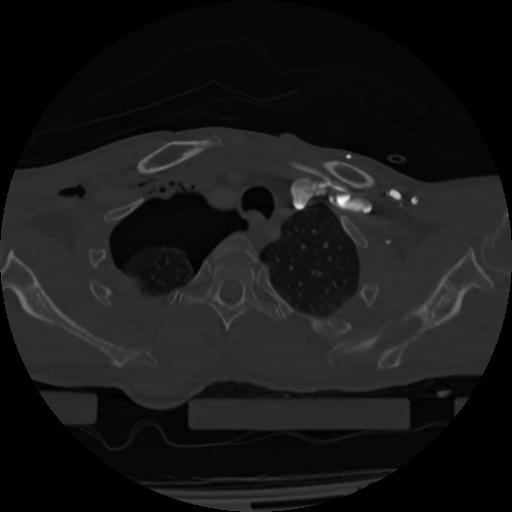

22 ANGIO,CE,Vol,0.5,ANGIO,,